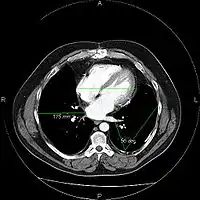

The same image following contrast adjustment, sharpening and measurement tags added by the system

A picture archiving and communication system (PACS) is a medical imaging technology which provides economical storage and convenient access to images from multiple modalities (source machine types).[1] Electronic images and reports are transmitted digitally via PACS; this eliminates the need to manually file, retrieve, or transport film jackets, the folders used to store and protect X-ray film. The universal format for PACS image storage and transfer is DICOM (Digital Imaging and Communications in Medicine). Non-image data, such as scanned documents, may be incorporated using consumer industry standard formats like PDF (Portable Document Format), once encapsulated in DICOM. A PACS consists of four major components: The imaging modalities such as X-ray plain film (PF), computed tomography (CT) and magnetic resonance imaging (MRI), a secured network for the transmission of patient information, workstations for interpreting and reviewing images, and archives for the storage and retrieval of images and reports. Combined with available and emerging web technology, PACS has the ability to deliver timely and efficient access to images, interpretations, and related data. PACS reduces the physical and time barriers associated with traditional film-based image retrieval, distribution, and display.